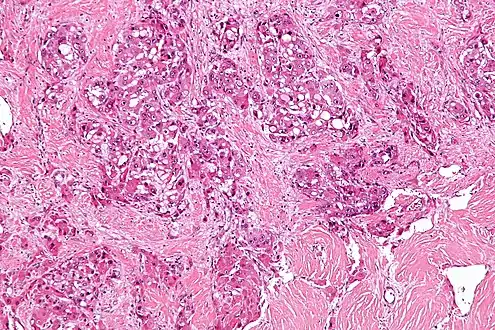

| Micrograph of fibrolamellar hepatocarcinoma showing the characteristic laminated fibrosis between the tumor cells with a low NC ratio. H&E stain. | |

The histopathology of FHCC is characterized by laminated fibrous layers, interspersed between the tumor cells. Cytologically, the tumor cells have a low nuclear to cytoplasmic ratio with abundant eosinophilic cytoplasm. Tumors are non-encapsulated, but well circumscribed, when compared to conventional HCC (which typically has an invasive border).